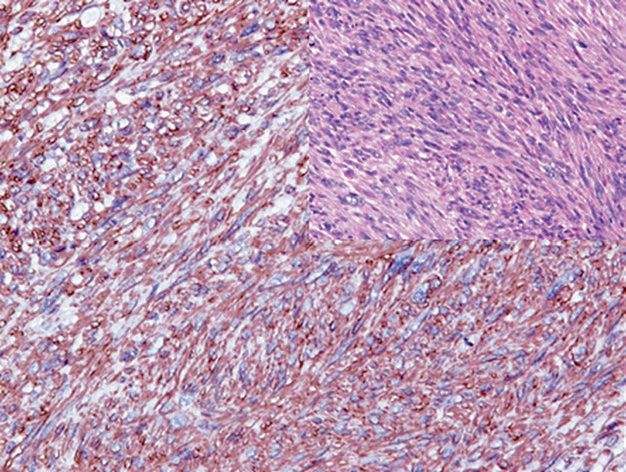

图1. 多形性横纹肌肉瘤,免疫组化desmin在瘤细胞的胞质显著表达。